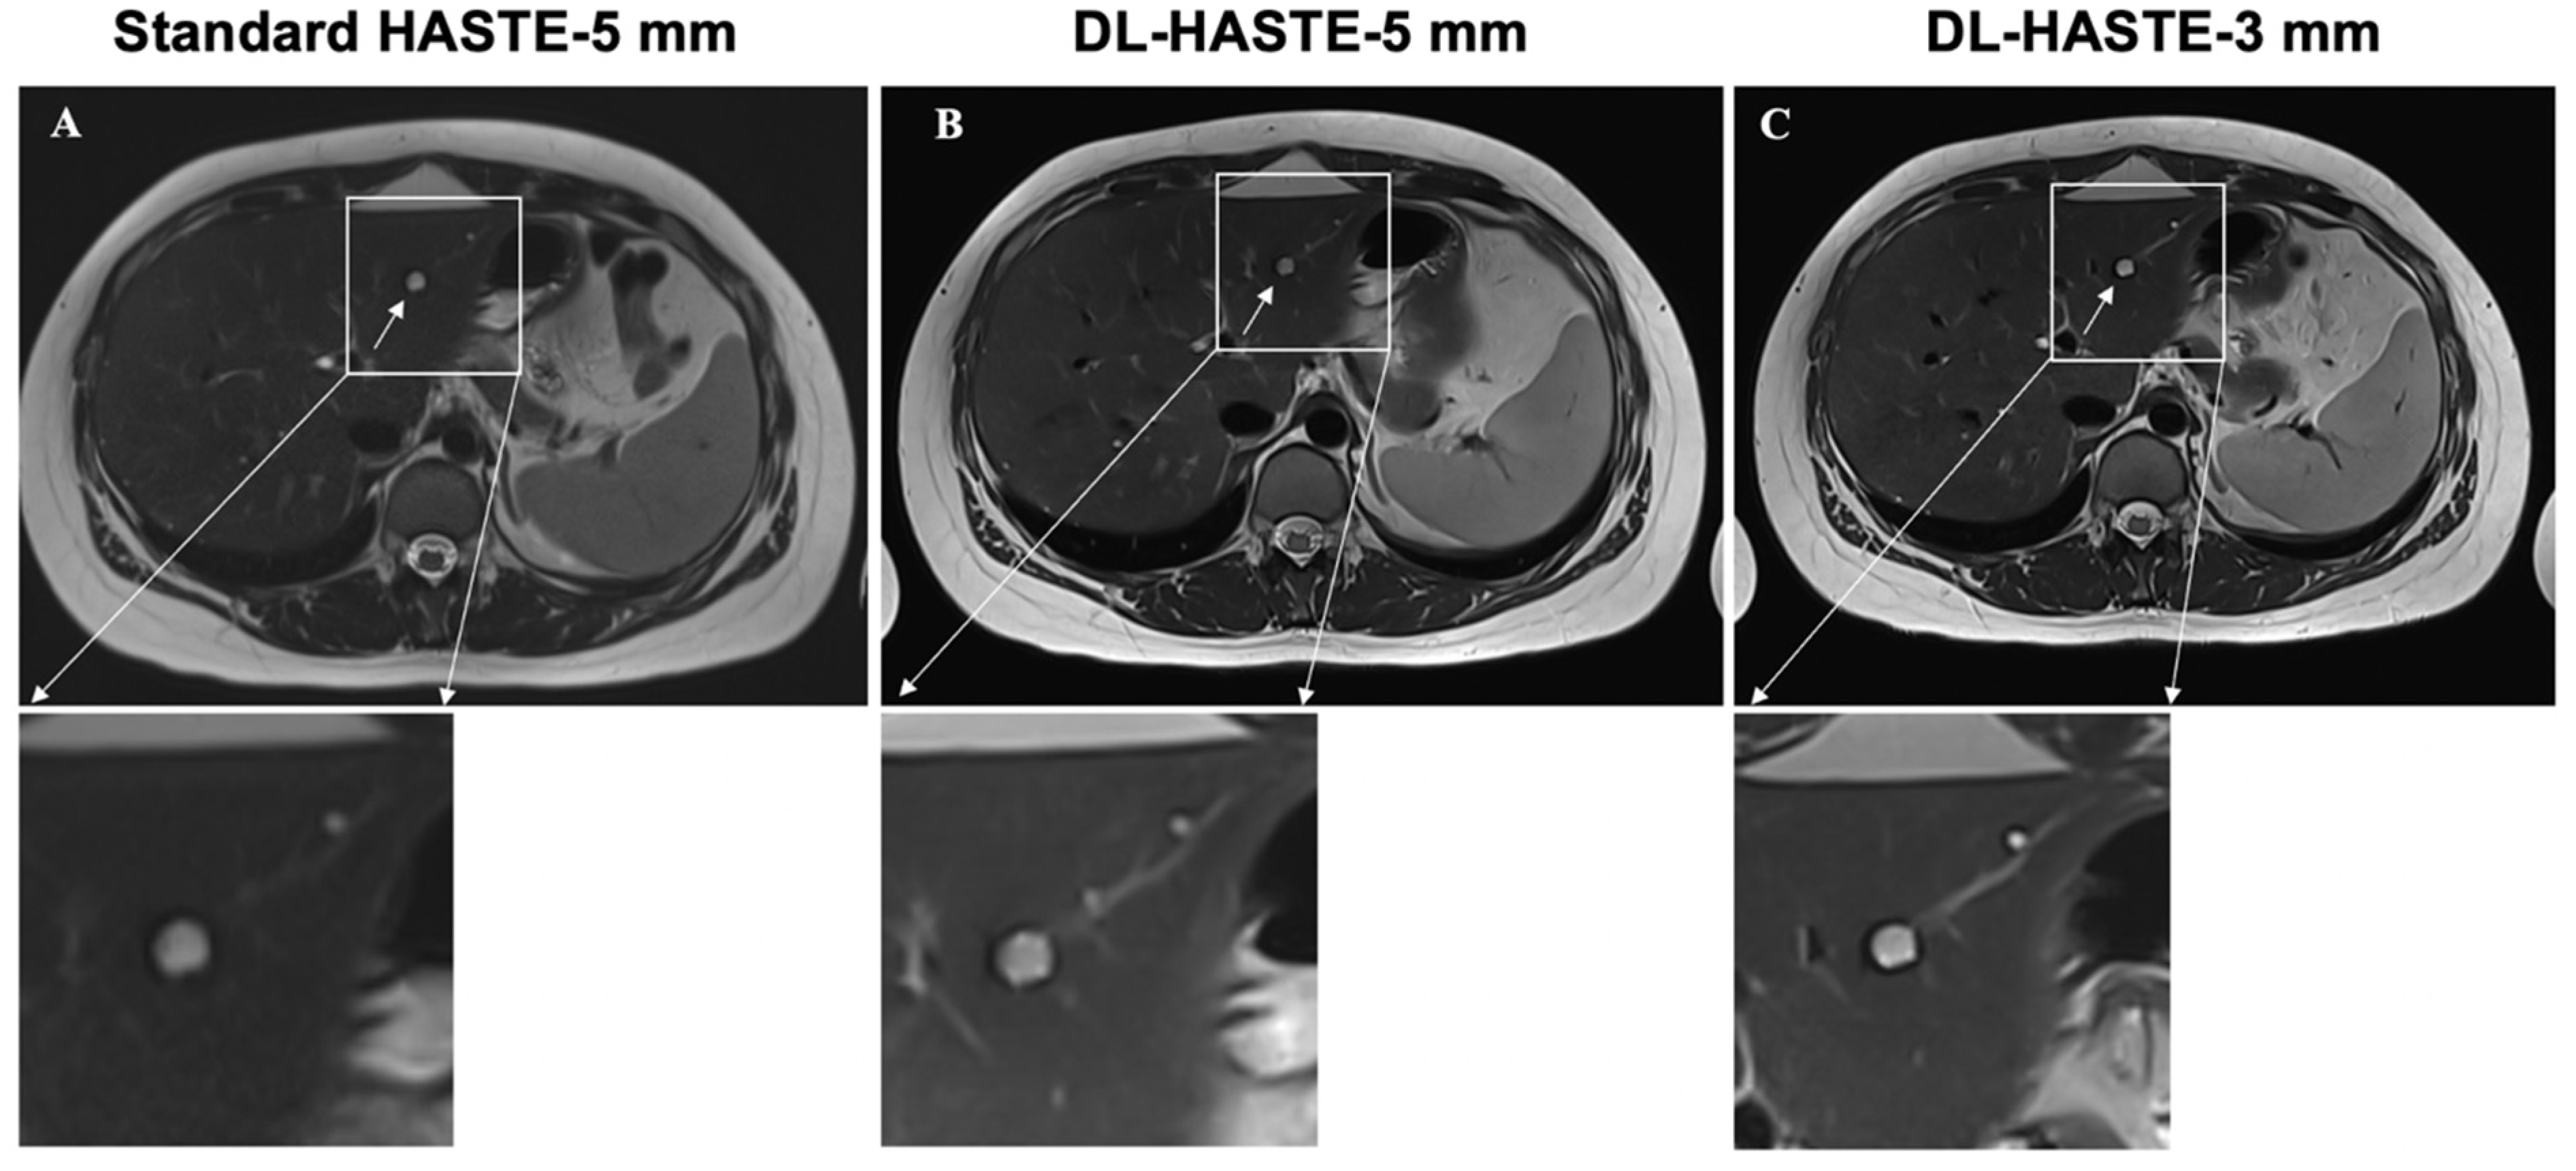

3.5. Lesion Detection